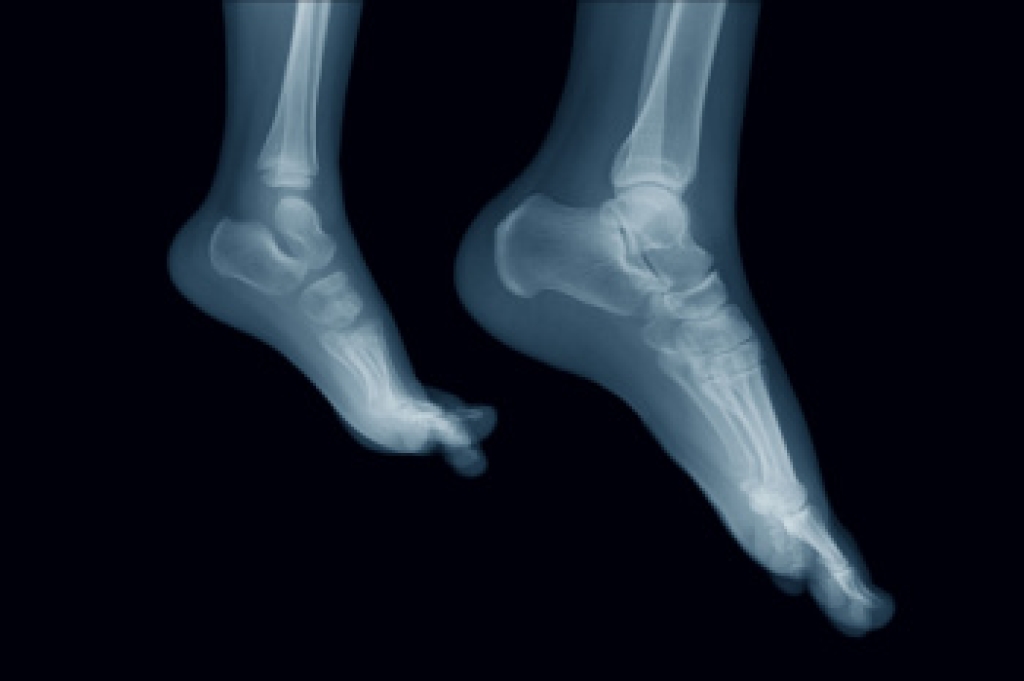

To figure out the cause of foot pain, podiatrists utilize several different methods. This can range from simple visual inspections and sensation tests to X-rays and MRI scans. Prior medical history, family medical history, and any recent physical traumatic events will all be taken into consideration for a proper diagnosis.